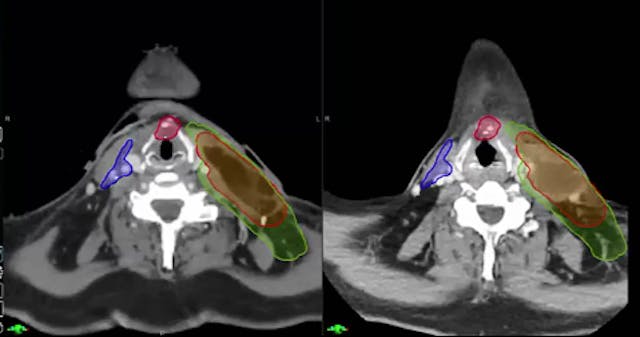

Head and neck cancerOropharyngeal cancer

HPV-associated squamous cell carcinoma

Tumor staging (T3 N2, AJCC)

Carcinoma with extranodal extension

PET/CT imaging

Radiation oncology case discussion